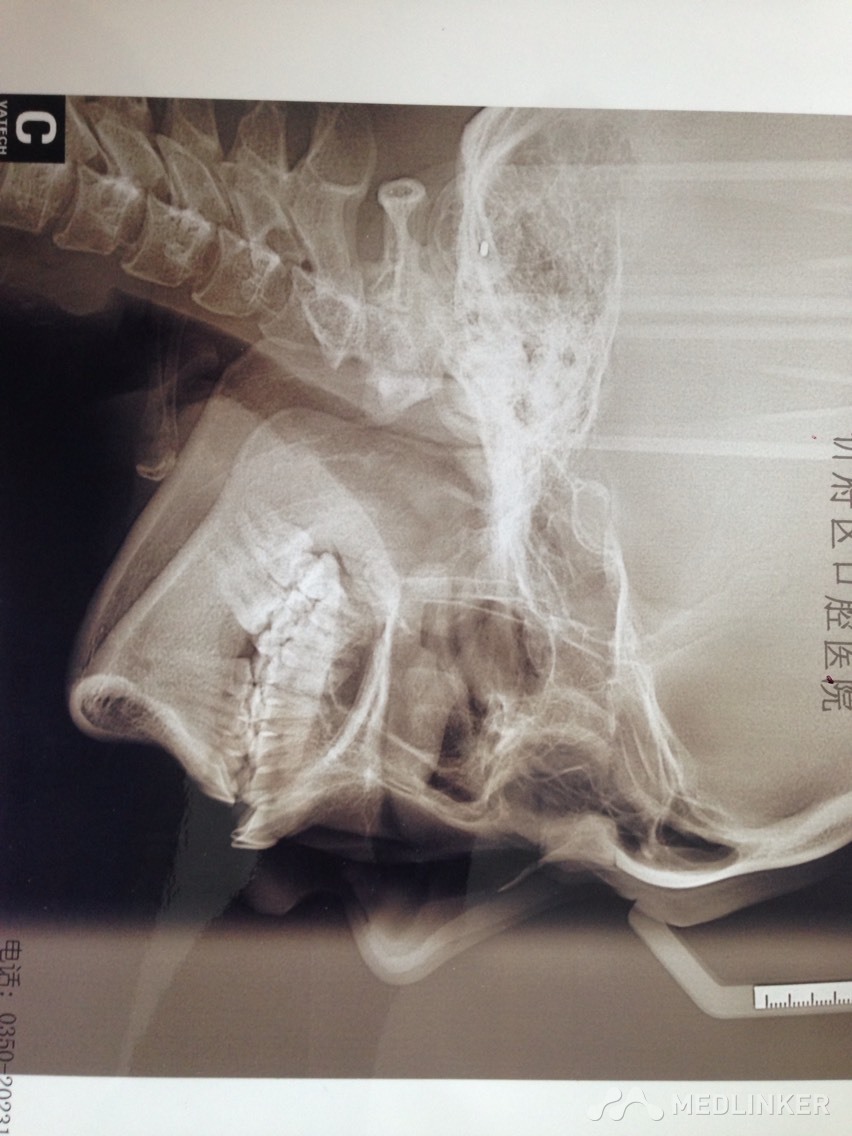

上颌前牙牙列拥挤,下颌前牙散在间隙,下颌双侧第一磨牙缺失多年,开合